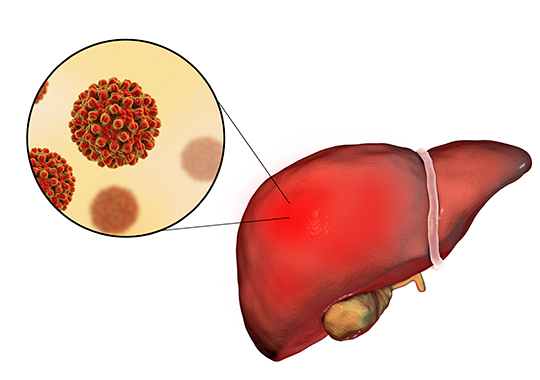

Canadian researchers working together to eliminate hepatitis C

Hepatitis C is a viral infection that attacks the liver, one of the abdominal organs that aids in digestion. It is regarded as a "silent" killer, as many people infected with hepatitis C feel no symptoms and are unaware that they carry the virus. Over time, some of these infected people will develop chronic hepatitis which can lead to liver damage, liver failure, and cancer.

It is estimated that about 400,000 Canadians are infected with the virus, or about 1% of our population. Globally, approximately 130-150 million people are infected, which results in an estimated 500,000 deaths each year.